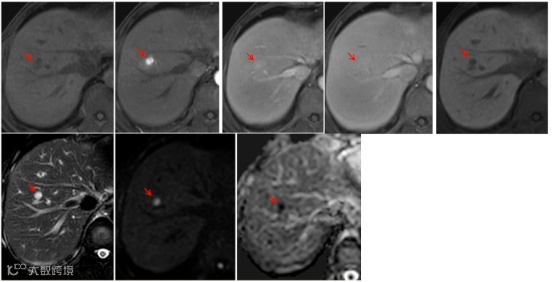

患者女性,59岁,HBV相关肝硬化。病例中scHCC显示出HCC的所有诊断特征,但门脉期无廓清,根据2024版原发性肝癌指南,对于EOB-MRI移行期或肝胆期“快出”也可作为辅助恶性征象,因此考虑scHCC,病理证实Edmondson-Steiner II级HCC[5]。

a:T2WI高信号,b:DWI弥散受限,c:动脉期非环形强化,d:门脉期无明显廓清,e:过渡期低信号,f:移行期低信号,直径为7.3mm[5]。